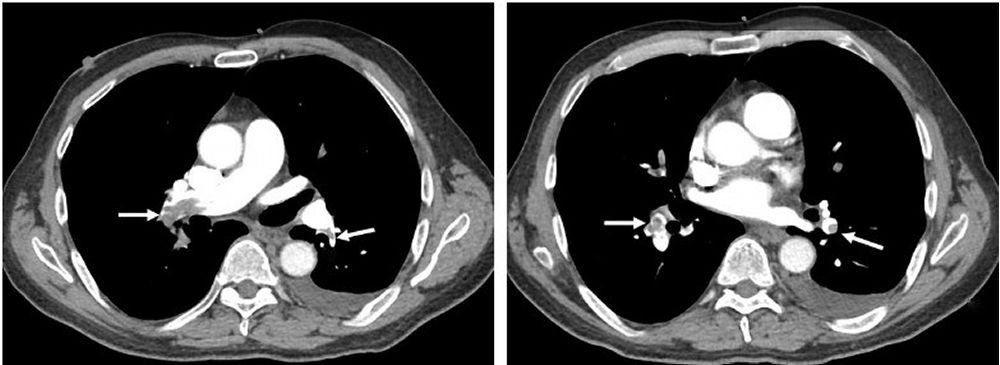

When suspicion is high, imaging tests provide definitive diagnosis. CT pulmonary angiography (CTPA) has become the gold standard, offering detailed images of pulmonary arteries to identify blockages. Ventilation-perfusion (V/Q) scanning, which compares air flow and blood flow in the lungs, is used when CT scanning isn't possible. Doppler ultrasound of the legs can detect DVT, while echocardiography may show signs of right heart strain caused by large pulmonary emboli.